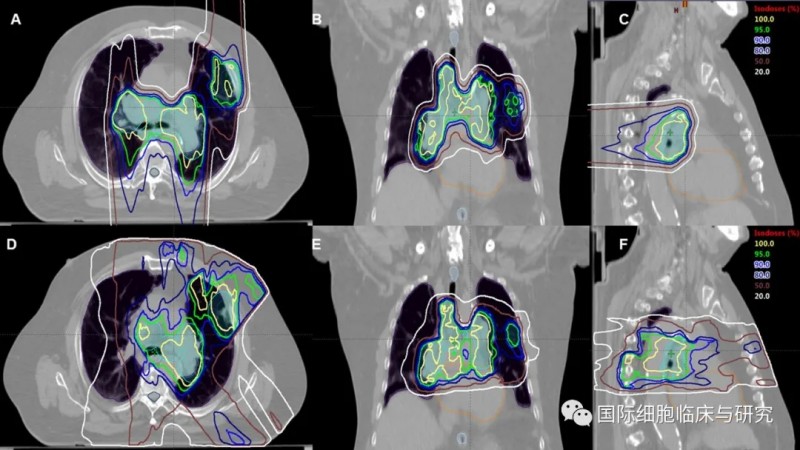

采用质子疗法治疗胸部肿瘤的照射范围

图片来源:acsjournals

接受胸部放疗时,患者的脊髓、心脏、食管及健康肺组织等部位暴露于放射线下,极易导致包括肺炎、食管炎、心包积液等在内的严重放射毒性。而采用质子疗法治疗小细胞肺癌,能够更好地将放射剂量集中于病灶部位,降低正常组织受到的辐射,减轻或减少不良反应。